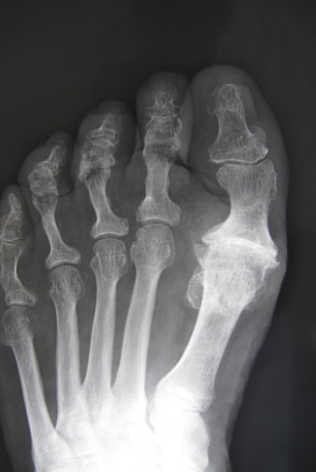

Radiographie

Une radigraphie du pied mettra en évidence l'arthrose de la base de l'Hallux